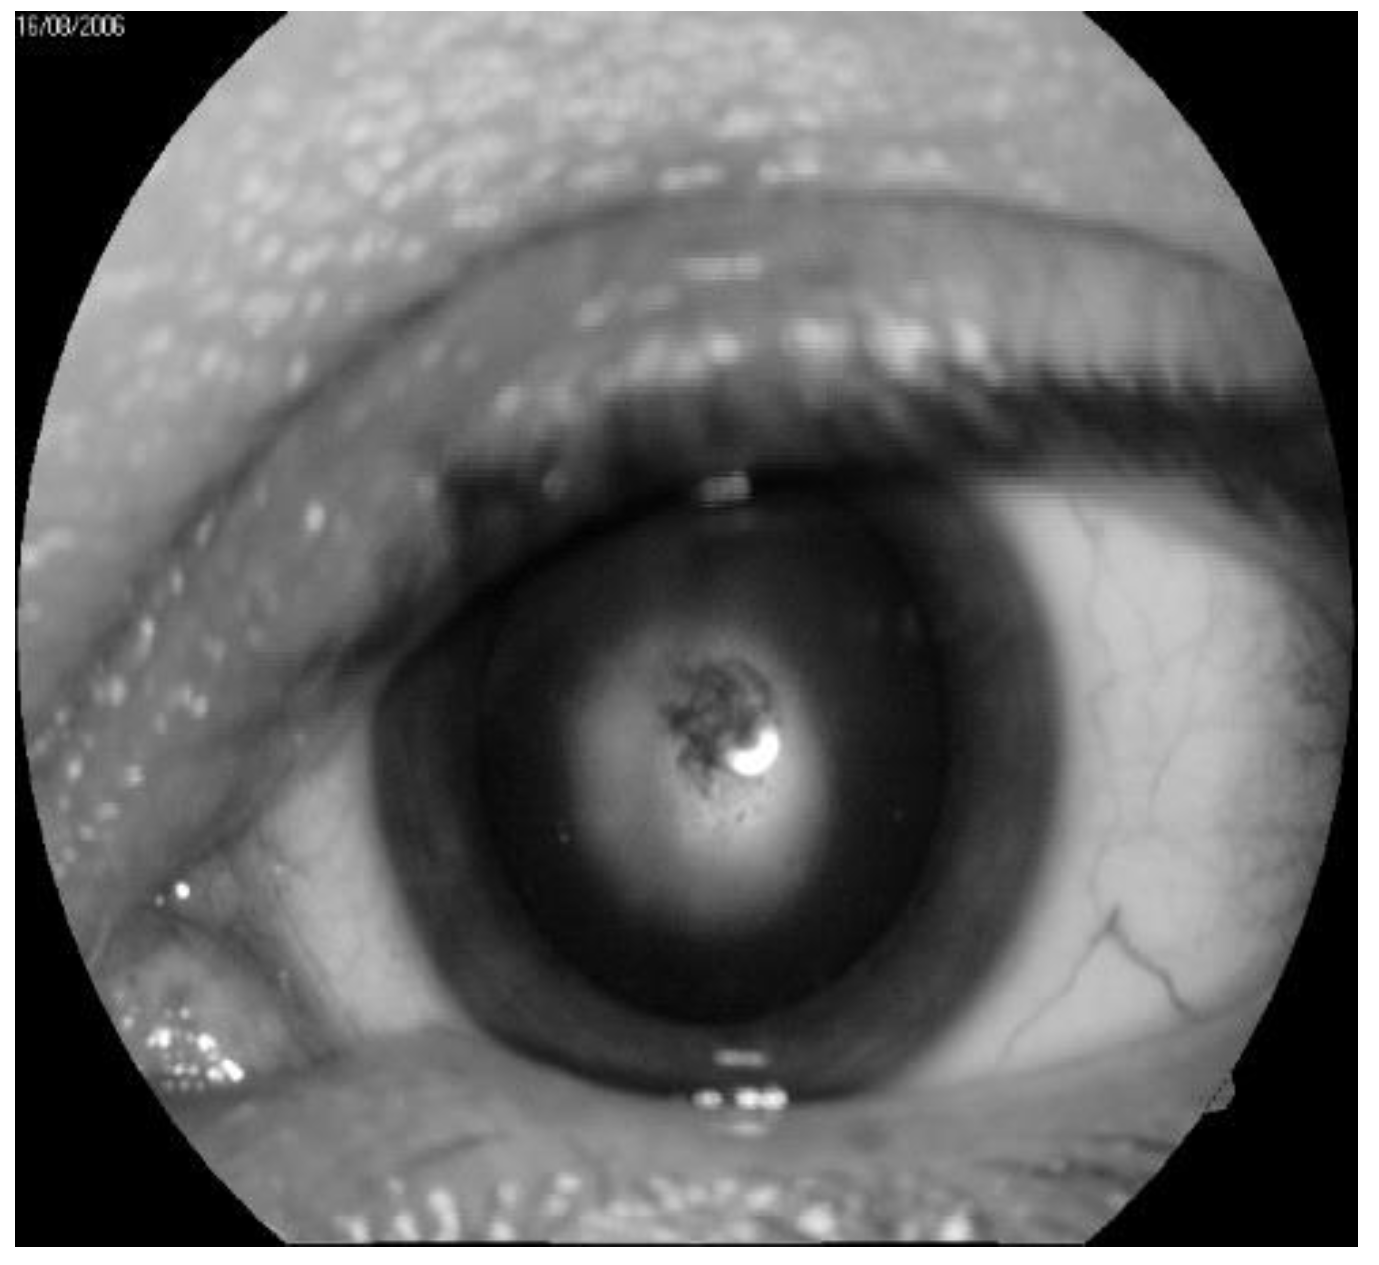

- Fedirko, P.; Babenko, T.; Kolosynska, O.; Dorichevska, R.; Garkava, N.; Grek, L.; Vasylenko, V.; Masiuk, S. Morphometric parameters of retinal macular zone in reconvalescents of acute radiation sickness (in remote period). Probl. Radiac. Med. Radiobiol. 2018, 23, 481–489. [Google Scholar] [CrossRef]